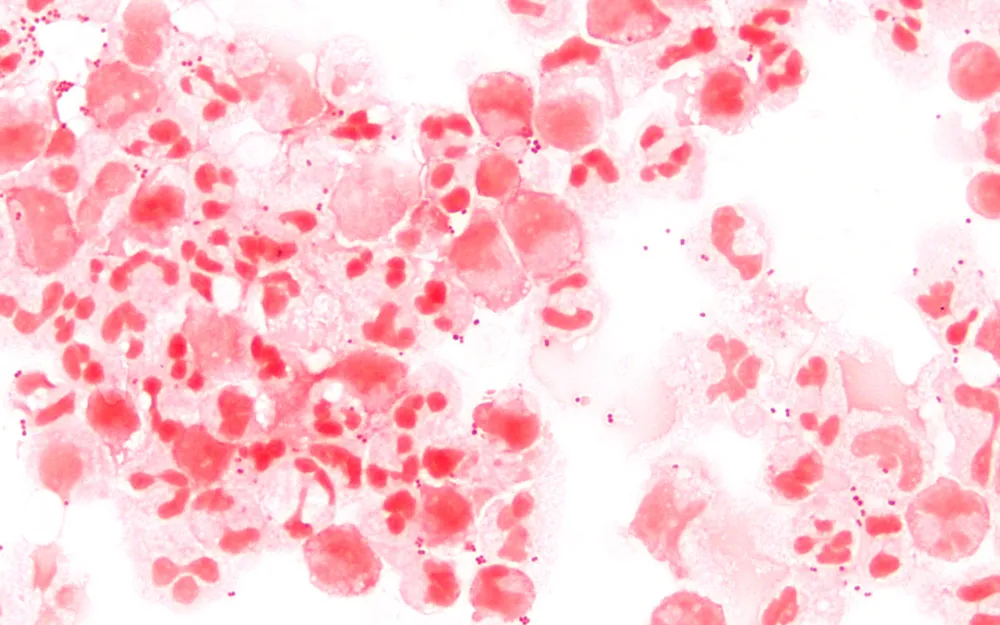

A meningite é uma infecção das membranas que recobrem o cérebro, conhecidas como meninges. Existem três tipos principais: bacteriana, fúngica e viral. A bacteriana é a mais grave, sendo causada principalmente pelo meningococo, pneumococo, haemophilus e mycobacterium tuberculosis. A fúngica é mais rara e associada a doenças que comprometem a imunidade, enquanto a viral é a mais frequente, geralmente causada por vírus, especialmente enterovírus.